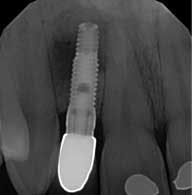

Upon examination, the No. 10 implant had a healing abutment placed and was noted to have circumferential loss of 3 mm to 4 mm of hard and soft tissue. This loss of tissue was significant enough that the collar of the implant fixture was now at the facial tissue margin. Also, tooth No. 9 had 5 mm of clinical attachment loss, and the tooth had been recently devitalized. A soft tissue lesion was also noted in the unattached tissue buccal to the apex of the No. 7 implant. The lesion appeared to be unproductive. A radiograph showed a large radiolucency around the apex of the No. 7 implant. The patient was referred to the periodontist to evaluate Nos. 9 and 10 for possible tissue graft and to find the origin of the lesion apical to the No. 7 implant.

The periodontist diagnosed the failed No. 7 implant with a large bone lesion around it, and he was not very confident in any significant gains of tissue in the No. 9 and 10 region. The patient at this point expressed a concern to have the definitive restorations placed without utilizing any implants, and for them to be as conservative as possible. To aid in the complexity, the patient had a limited time (10 days) to complete any treatment before he moved 2,000 miles away.

The patient was treatment planned alongside the periodontist to remove the No. 7 implant and graft the bone lesion. A cover screw was planned to be placed on the No. 10 implant and bury it under the soft tissue for esthetics. Two ceramic (e.max) Maryland bridges were placed to restore the missing laterals, bonding to both adjacent teeth. The possible complications were explained to the patient, and he consented to treatment. Initial data was gathered including photo grafts, mounted cast, and a diagnostic wax-up. The restorative plan was to be completed using a Planmeca E4D scanner and mill to fabricate the restorations.